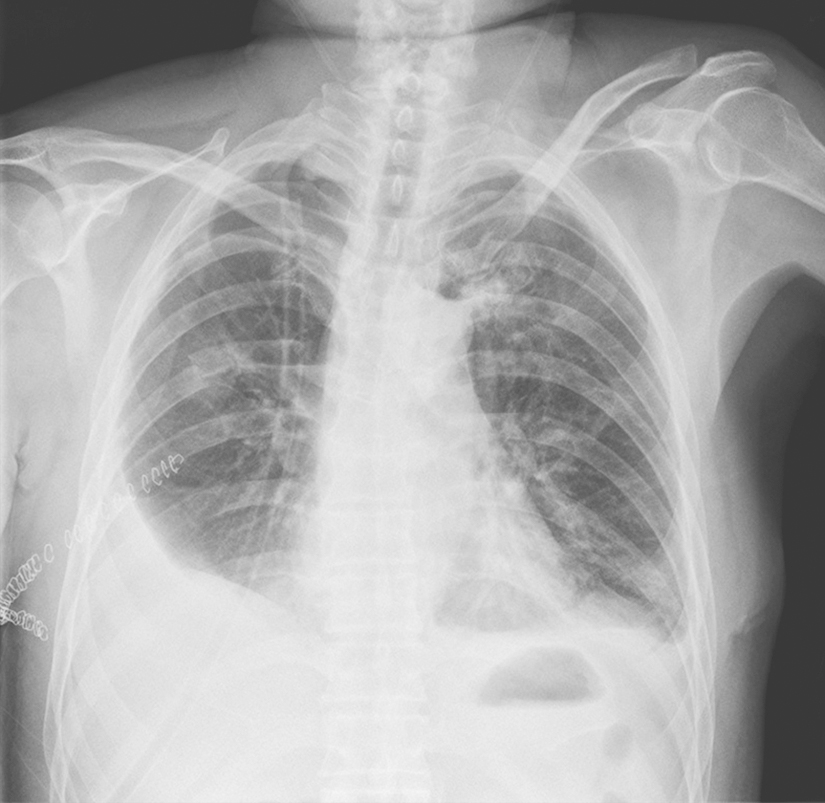

胸腔积液量在0.3~0.5L时,X线仅见肋膈角变钝;积液量多时显示外高、内低、凹面向上的积液影。平卧时积液影散开,使整个肺野透亮度降低。液气胸时可见气液平。大量积液时,纵隔推向健侧,患侧肺野透光度减低。积液包裹时可见边缘光滑的阴影,不随体位改变而变化(图2-13-2)。

图2-13-2 渗出性胸膜炎胸片